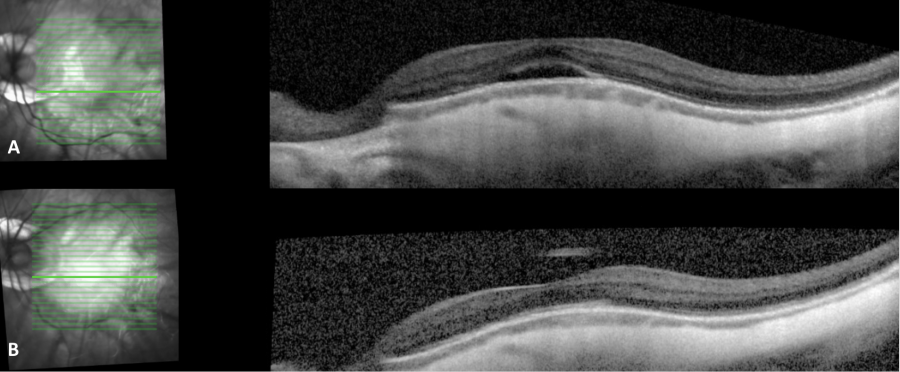

DSM management focuses on reducing subretinal fluid (SRF), but no effective treatment for this complication has been established. Three monthly injections of aflibercept may improve best-corrected visual acuity (BCVA) and reduce central subfield thickness on OCT,[13] but bevacizumab and ranibizumab have proven ineffective at improving BCVA or subretinal fluid.[6][16][17] There are also limited reports of mineralocorticoid receptor antagonists successfully resolving serous foveal detachments.[18] Photodynamic therapy (PDT) trials for subretinal fluid associated with DSM have conflicted over the efficacy of this treatment.[6][19] Additionally, vitrectomy may aid in the transient resolution of sub-retinal detachment in DSM patients.[20] Due to the lack of a proven treatment, many physicians elect to observe asymptomatic or mildly symptomatic cases. Oftentimes the subretinal fluid resolves and recurs intermittently over time (Figure 1). A study[6] on 56 eyes with DSM noted that there was no significant improvement in BCVA or complete resolution of subretinal fluid with bevacizumab, ranibizumab, or PDT; and the authors concluded that DSM 'is often associated with chronic SRF, for which no effective treatment is current(ly) available'.

- ↑ Image courtesy of Danny A. Mammo MD